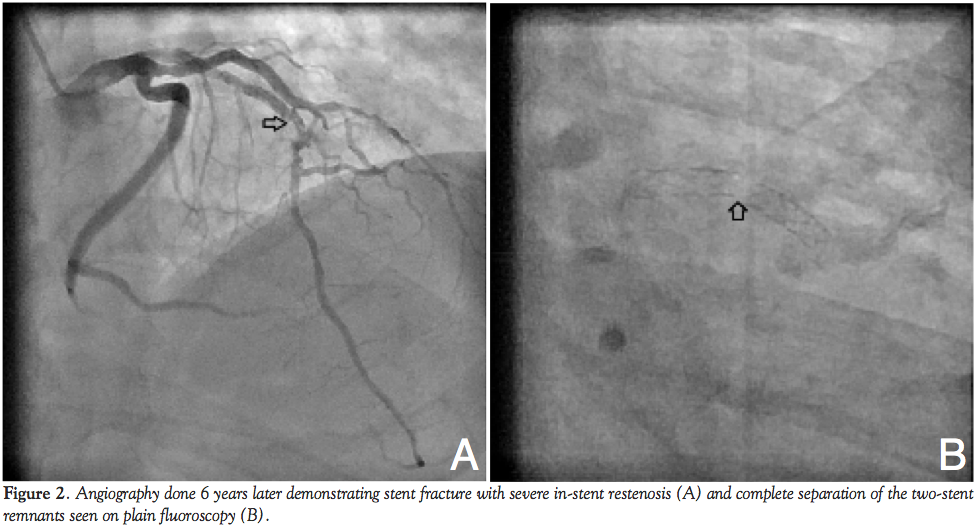

The patient presented with an acute anterior wall ST-elevation myocardial infarction 6 years later, for which he was thrombolysed with streptokinase within 2 hours with good ST segment resolution. Coronary angiography at our institute (3 days following the MI) revealed a complete fracture of the stent at its middle part, with total separation of the 2 portions of the stent. The separated stent pieces in the mid LAD were easily visible during plain fluoroscopy (Figures 2A and B). The patient underwent CABG and successfully received a left internal mammary artery graft to LAD (Figure 3).

Though the exact mechanism responsible for stent fracture is not well understood, specific anatomic and technical factors play an important role. Overexpansion may lead to stretching and deformation while mechanical fatigue in areas of coronary artery tortuosity or excessive artery motion leads to constant compression, kinking and shearing, predisposing to fracture. Hence, stent fractures are most commonly reported in the right coronary artery (related to its mobility), overlapping and long stents, those deployed at high inflation pressure, or in vein grafts.3,8 Though our case had a 28 mm long Cypher stent implanted in the LAD, the exact cause of stent fracture remains conjectural. It is possible that slight changes in vessel angulation, which occur after stent implantation, may create a distorting force predisposing to stent fracture over time. Although intravascular ultrasound and multislice computed tomography are considered more sensitive than routine coronary angiography to establish the diagnosis and mechanism of stent fracture, often (as also in our case), diagnosis is evident even on plain fluoroscopy, especially when the fracture is complete.